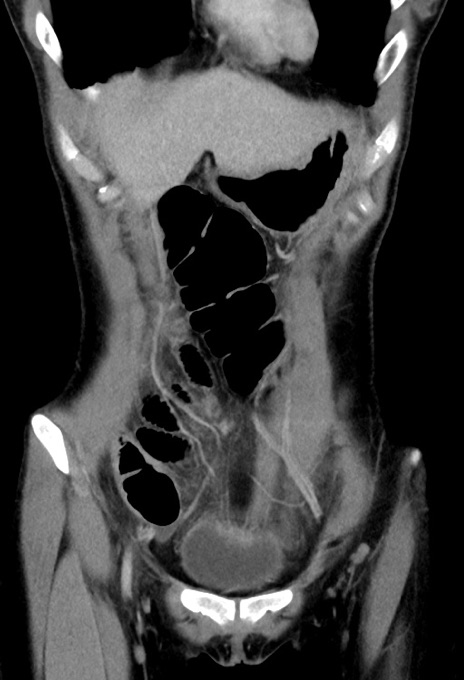

横断像

【症例】20歳代女性

【主訴】嘔吐、下腹部痛

【現病歴】昨日夕食後に嘔吐し下腹部痛が出現。本日になっても嘔吐持続し改善しないため来院。

【身体所見】意識清明、BT 37.2℃、BP 108/67mmHg、腹部:平坦、やや硬、下腹部正中から右にかけて圧痛あり、反跳痛軽度あり、tapping pain(+)。

【データ】WBC 13600、CRP 14.94